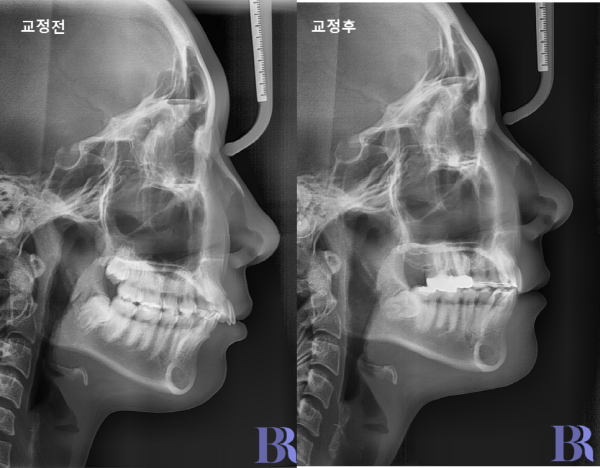

편측발치 교정 : 교정 전후 옆모습입니다.

입술라인이 과도하지 않고 자연스럽게 들어갔습니다.

교정전후 옆모습 사진입니다.

입술라인이 과도하지 않고

자연스럽게 들어갔습니다

위 환자분 같은 경우 아랫니까지

발치를 진행했다면 자칫

입술이 과하게 들어갔을 겁니다.

교정 전후 옆모습입니다.

윗니와 아랫니 앞뒤 차이가

정상적으로 줄어들었습니다.

교합도 긴밀하게 잘 맞아들어

가는 것을 볼 수 있습니다.